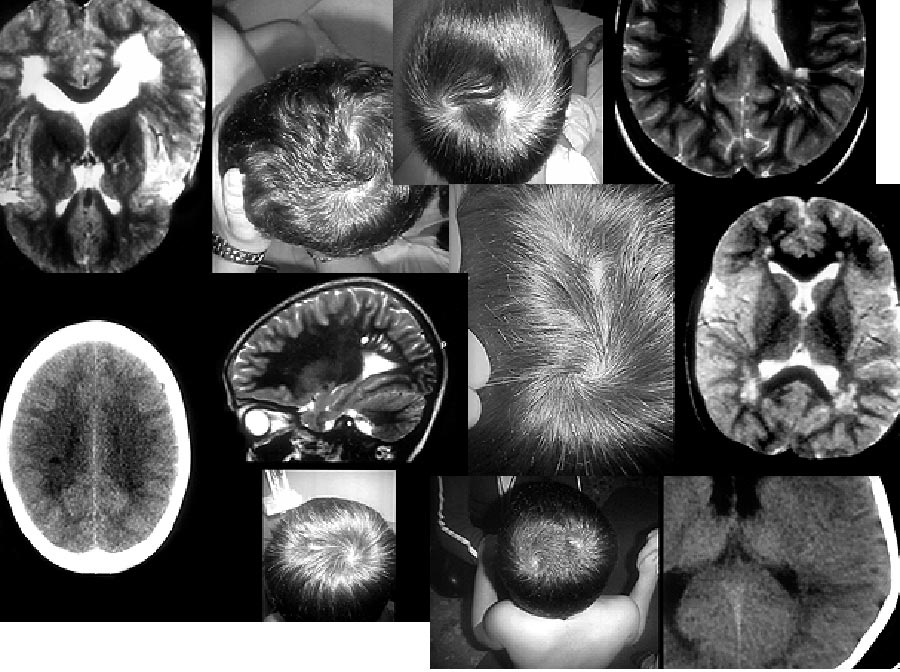

• Dos Remolinos Cortes De Pelo Para Niños Con Remolinos